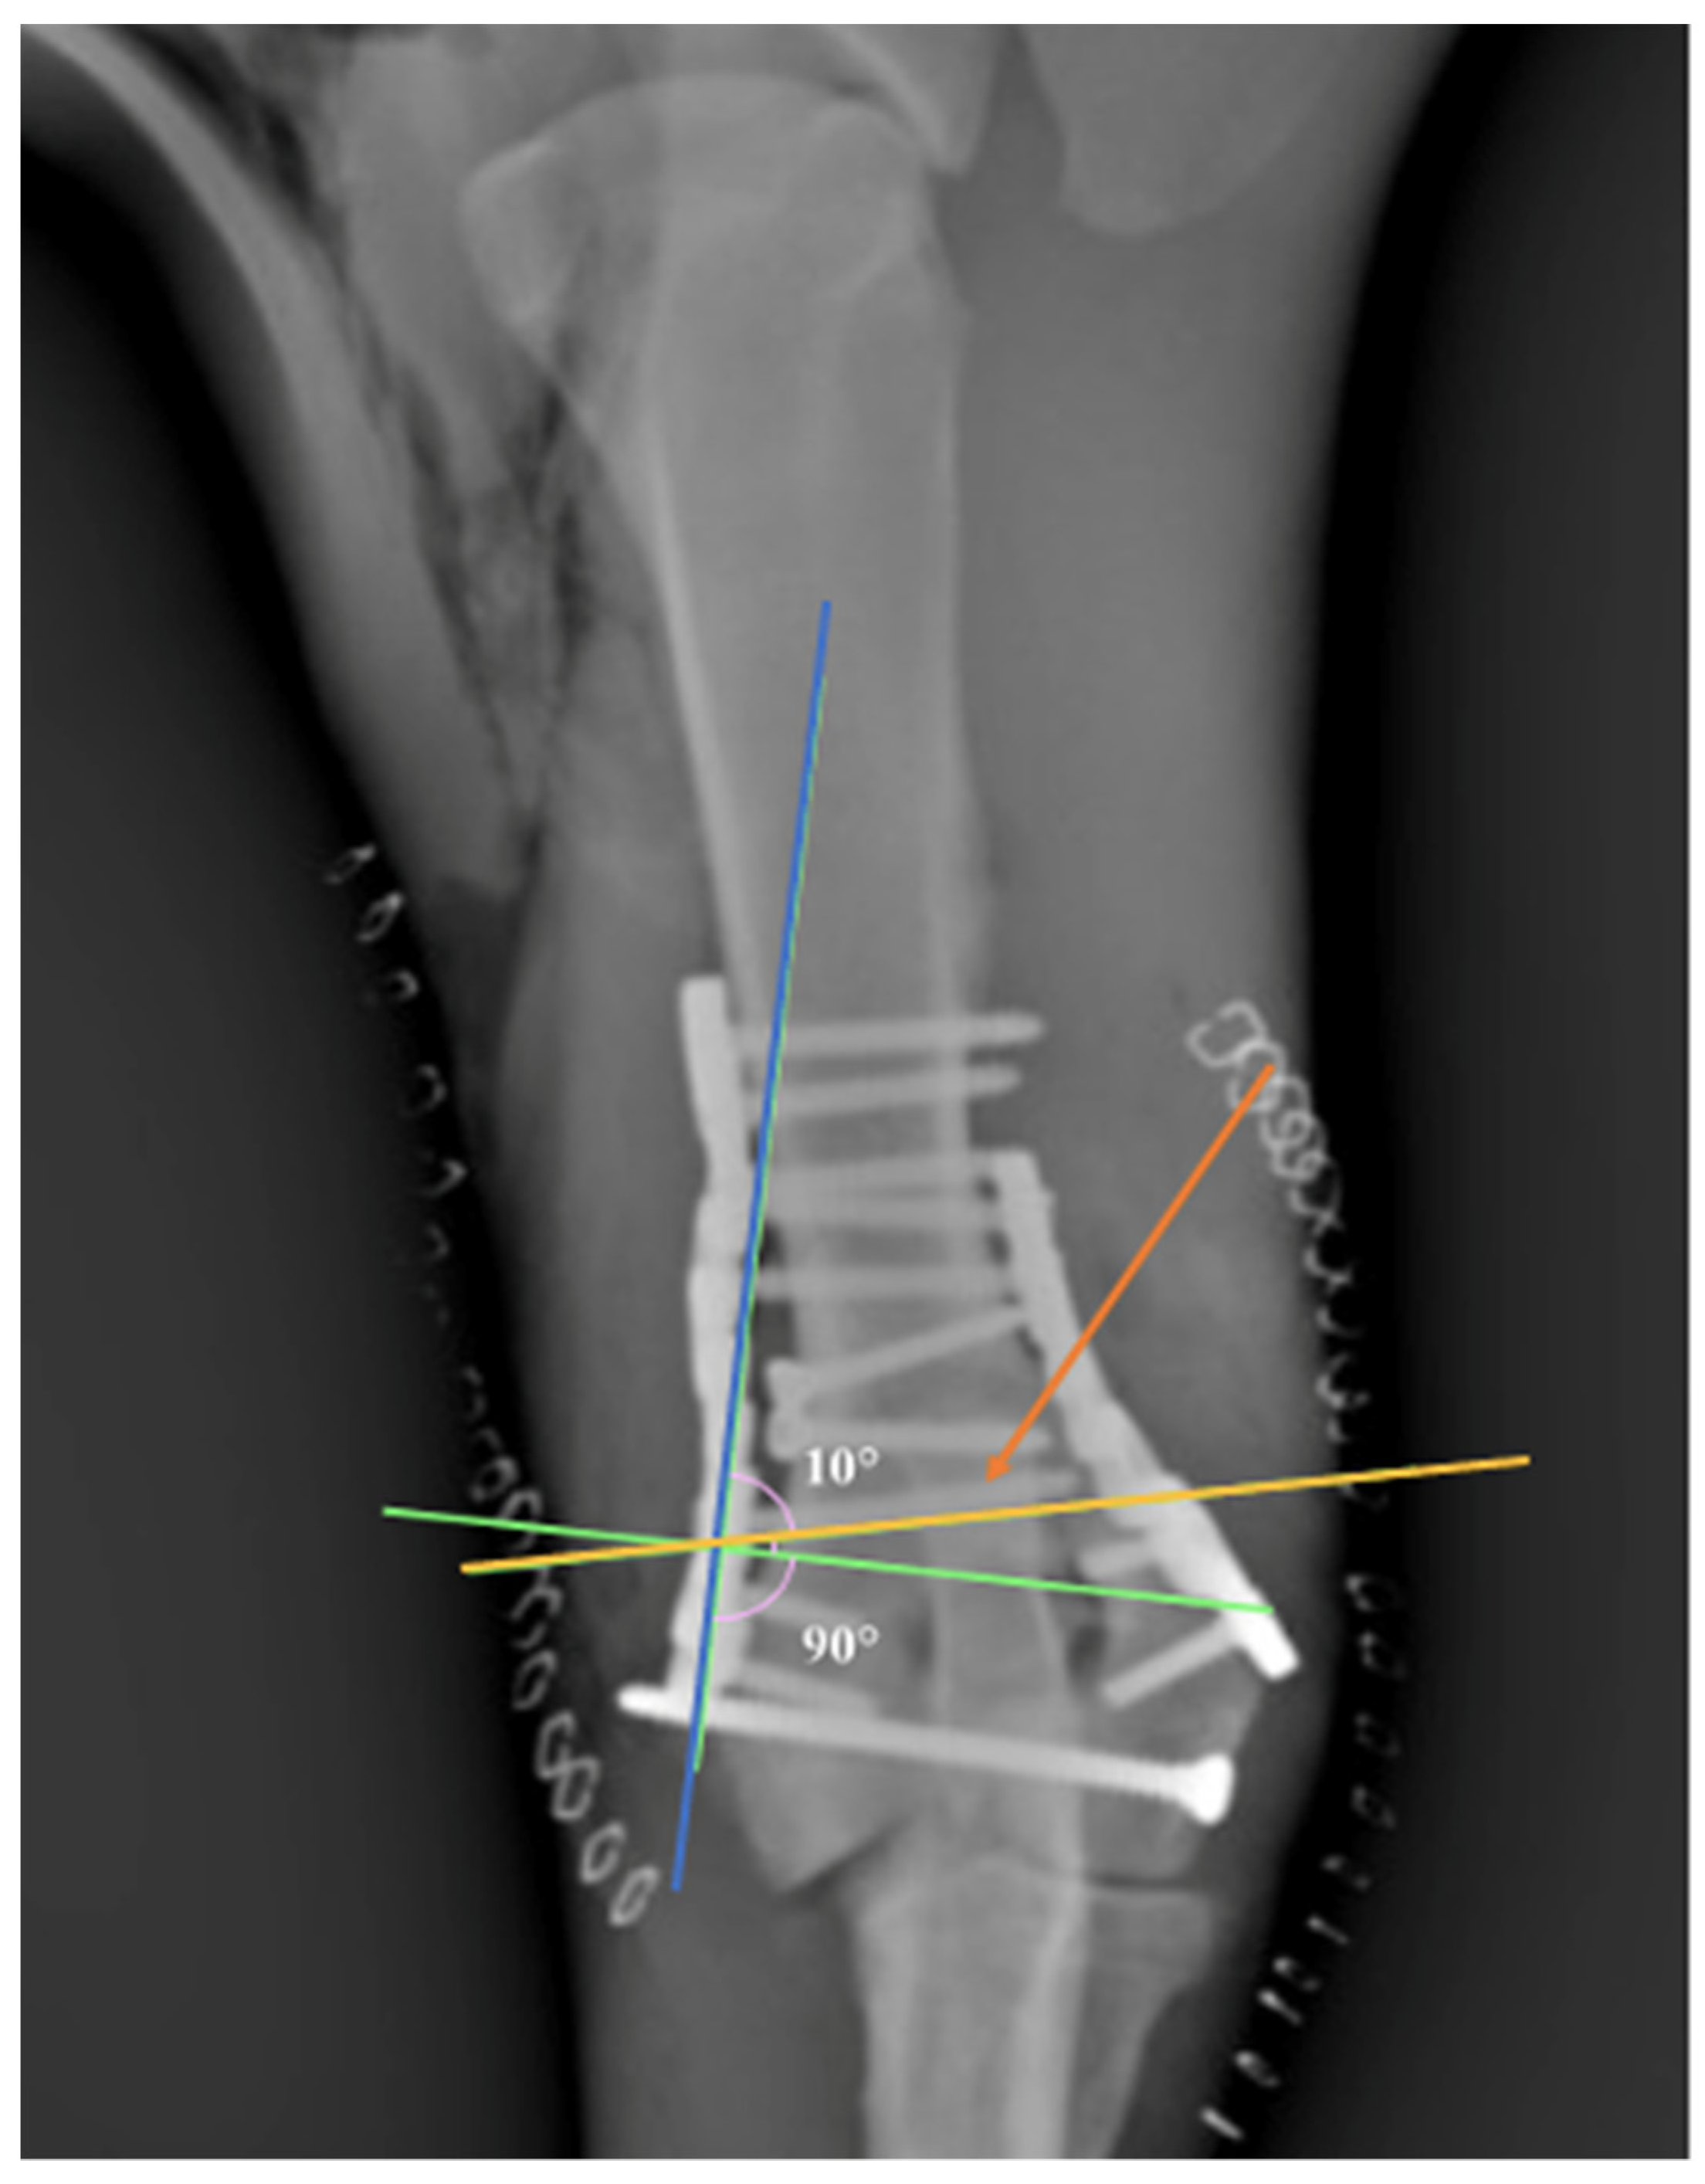

Figure 2.

Note the angulation (10°) of the screw (orange arrow) in an attempt to avoid the joint space. Note that the screw inserted at 90° could invade the joint space (green line). Yellow line: screw direction. Blue line: orientation of the plate’s hole.

Plating the distal humerus sometimes requires extreme contouring of the plate [8]. In human medicine, the use of anatomical pre-contoured locking implants seems to be very useful in order to increase the stability of the construct and reduce soft tissue irritation and surgical time [28]. The contouring of locking plates is not strictly necessary; nevertheless, we found it very useful to contour the plates to better address the bone in order to limit the juxtarticular soft tissue impingement. The proper shaping of the PAX RP is achieved using the PAX reconstruction bending plier. This device allows the plate to be bent in multiple planes, while preventing polyaxial plate holes from deformation [14]. The bending plier is necessary in order to avoid multiple bending corrections in the attempt to reproduce the complex footprint of the distal humerus, as repetitive bending may lead to metal fatigue in the contoured areas, increasing the risk of premature plate failure [29]. The plate contouring reported in previous studies seems to condition the direction of the locking screws, while the direction of the PAX system screw is less influenced by the plate contouring. Garcia et al. reported the application of medial epicondylar plates on the medial aspect of the humerus, while the lateral epicondylar plates were applied on the lateral aspect in 12 fractures and caudally in 15 fractures [9]. We hypothesized that the authors, not being able to direct the locking screws using the locking compression plate system (LCP), were forced to apply the plate in such a way to avoid invading the fracture lines or joint space. In our cases, the parallel application of the plates on true medial and lateral bone sides has been made possible by the use of PAX system (Figure 2).

The polyaxial advanced locking system (PAX; Securos Surgical AmerisourceBergen, Fiskdale, MA, USA) is an implant made of titanium alloy (Ti6Al4V) that should determine theoretically minimal tissue reaction with a potentially lower infection incidence [13]. The PAX system was designed with the particular benefits of locking plate technology while offering a polyaxial insertion option of the screws, which can be angled multidirectionally. The PAX-system’s screw locking mechanism is achieved as the sharp threads of the harder screw head engages and “cut” threads within the holes of the plate during insertion. As in other polyaxial implants, the best locking mechanism is achieved when the screw is inserted perpendicular to the hole of the plate, but the multidirectional screw insertion with an angulation up to 10° within the plate in the Pax System allows an appropriate locking strength [11,12,14,15]. The possibility to angulate the screw is particularly advantageous when screws need to be directed away from articular surfaces, fracture lines or when challenging fracture site exposure would have made a perpendicular screw insertion difficult [12].